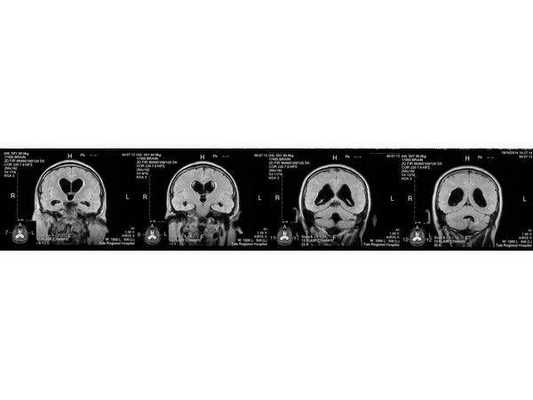

По заключению МРТ от 14.05.2013, после операции в левом полушарии мозжечка появились кистозно-глиозные изменения (на месте повреждённых нейронов образовались рубцовая ткань), а также выраженная внутренняя асимметричная гидроцефалия (избыточное скопление спинномозговой жидкости в полости черепа).

- МРТ в динамике показывает постепенное сужение желудочковой системы на 2 мм. Для сравнения представлены снимки МРТ от 14.05.2013 и от 16.10.2014.